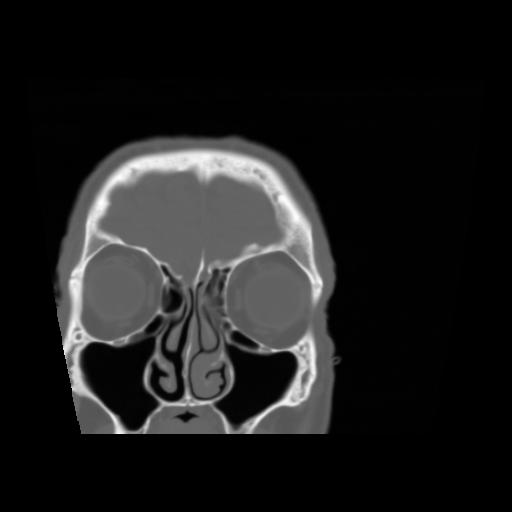

5 CEREBRO,,Coronal,3.000,CEREBRO,Coronal,